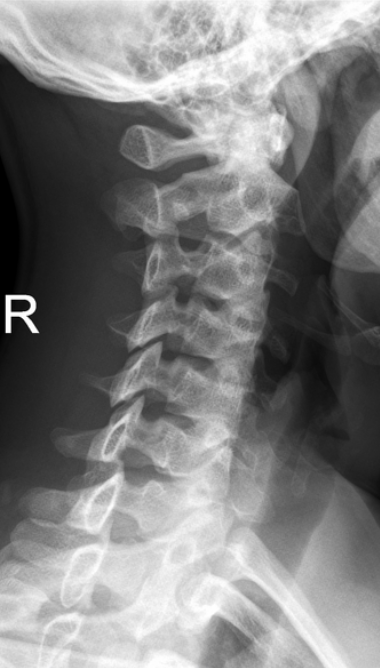

퇴행성 변화(척추증)

- 경추 5-6번 사이 경미하게 좁아진 디스크

- 경추 6-7번 사이 좁아진 디스크와, 갈고리처럼 변형된 골극(spur)

척추분리증

- c-2 뒤쪽 좁은 관절부 결손, 분리